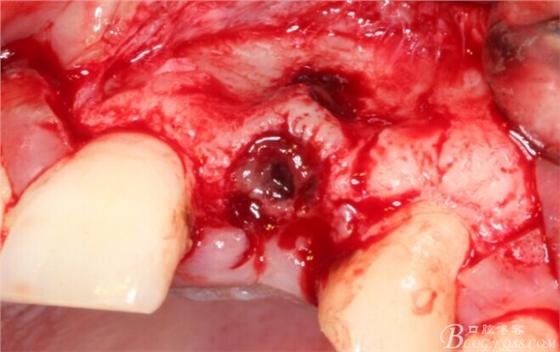

于是我果斷告知患者,手術(shù)失敗了,不能拖延,如不及時(shí)處理,炎癥繼續(xù)發(fā)展會(huì)很快波及鄰牙牙槽骨。患者接受我的建議。切開翻瓣,骨粉及生物膜消失了,骨吸收嚴(yán)重,幸運(yùn)的是,因?yàn)樘幚砑皶r(shí),鄰牙骨支持依然存在。

徹底掻刮。